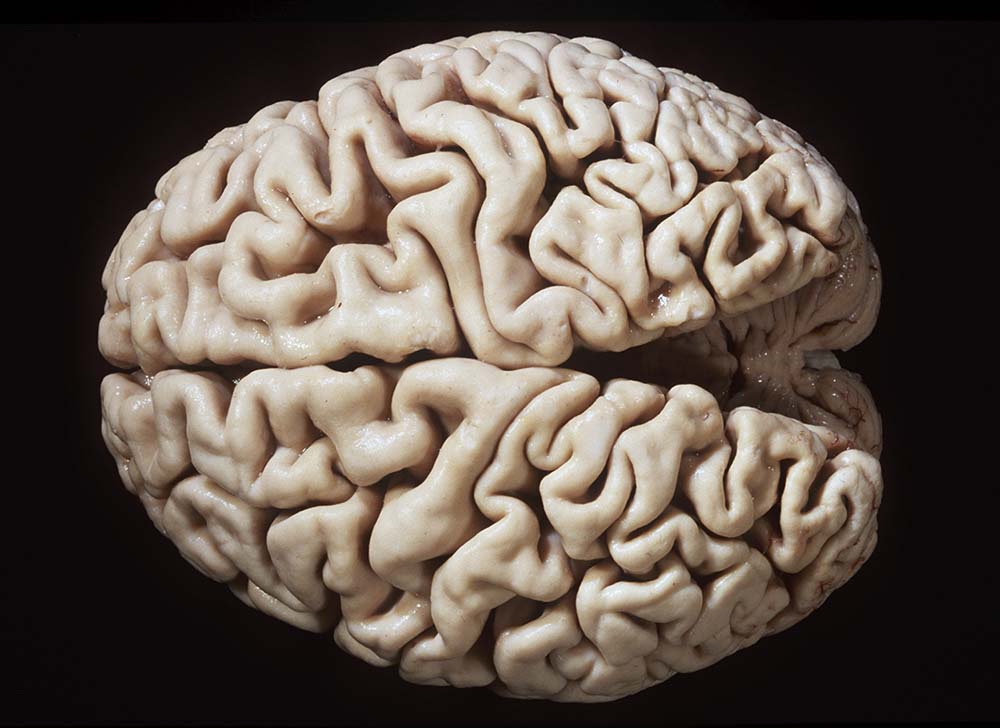

Gehirne von Alzheimer Patienten sind makroskopisch durch eine kortikale Atrophie (vor allem temporo-parietal) charakterisiert. Weiter findet sich meist eine deutliche Atrophie von Hippocampi und Mandelkernen. Diese geht einher mit einem Hydrocephalus internus (e vacuo), wobei vor allem die Temporalhörner der Seitenventrikel betroffen sind.